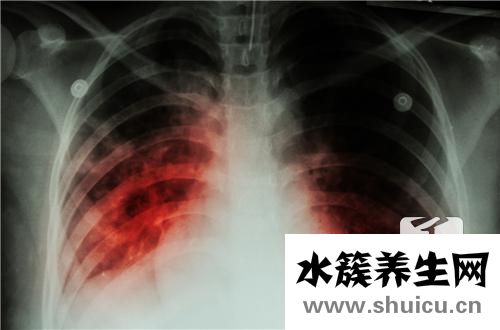

肺結(jié)核是目前臨床醫(yī)學(xué)上非常常見(jiàn)的呼吸系統(tǒng)傳染病,屬于屬于B類(lèi)傳染病。患有肺結(jié)核的患者會(huì)出現(xiàn)嗜睡、咳嗽和咯血,并且肺結(jié)核有病史。本文詳細(xì)介紹了肺結(jié)核前額疾病、臨床癥狀及其分析和分期。我們來(lái)看看這幾個(gè)方面。

結(jié)核病是由結(jié)核病分枝桿菌造成的漫性傳染性疾病,可侵及很多內(nèi)臟器官,以肺臟結(jié)核病感染更為普遍。排菌者為其關(guān)鍵的病原體。身體感染結(jié)核桿菌后不一定病發(fā),當(dāng)?shù)挚鼓芰p少或體細(xì)胞介導(dǎo)的超敏反應(yīng)提高時(shí),才可能造成臨床醫(yī)學(xué)病發(fā)。若能立即確診,并予有效醫(yī)治,大多數(shù)可獲臨床醫(yī)學(xué)治愈。

3、肺結(jié)核的分析和分期

(1)肺結(jié)核分型 血壓原發(fā)型肺結(jié)核(Ⅰ型) 肺內(nèi)外滲變病、淋巴管炎和肺部淋巴腫大的杠鈴狀改變的原發(fā)綜合征,少年兒童多見(jiàn),或僅主要表現(xiàn)為肺部和縱隔淋巴結(jié)腫脹。血液血液循環(huán)播散型肺結(jié)核(Ⅱ型) 包含亞急性粟粒性肺結(jié)核和漫性或急性血液循環(huán)播散型肺結(jié)核兩種類(lèi)型。亞急性粟粒型肺結(jié)核:兩肺散在的粟粒尺寸的黑影,尺寸一致相對(duì)密度相同,遍布勻稱(chēng)的粟粒狀黑影,隨病期進(jìn)度,可相互之間結(jié)合;漫性或急性血液循環(huán)播散型肺結(jié)核:兩肺出現(xiàn)大小不一、新老變病不一樣,遍布不勻稱(chēng),邊沿模糊不清或鋒利的包塊和索條黑影。補(bǔ)充繼發(fā)性型肺結(jié)核(Ⅲ型) 本型中包含變病以繁衍主導(dǎo)、侵潤(rùn)變病主導(dǎo)、奶酪變病主導(dǎo)或裂縫主導(dǎo)的多種多樣改變。侵潤(rùn)型肺結(jié)核:X線(xiàn)常為云絮狀物或小塊狀侵潤(rùn)黑影,邊沿模糊不清(滲出性)或包塊、索條形(增殖性)變病,大面積實(shí)變或球型變病(奶酪性—由此可見(jiàn)裂縫)或增厚;漫性化學(xué)纖維裂縫型肺結(jié)核:多在兩肺上端,亦為一側(cè),很多化學(xué)纖維增生,在其中裂縫產(chǎn)生,呈破棉花狀,肺組織收攏,肺門(mén)邊提,肺部影呈“楊柳樹(shù)樣”改變,胸膜肥厚,膈肌坍塌,部分代償性肺氣腫。負(fù)重結(jié)核性胸膜炎(Ⅳ型) 病側(cè)胸腔積液,少量為肋膈角變淡,適量的以上積血為高密度黑影,內(nèi)緣呈弧型。

(2)分期付款 血壓進(jìn)度期 探索與發(fā)現(xiàn)的活躍性肺結(jié)核,隨診中疾病增加擴(kuò)大,出現(xiàn)裂縫或裂縫擴(kuò)張,痰菌查驗(yàn)轉(zhuǎn)呈陽(yáng)性,發(fā)熱等臨床表現(xiàn)加劇。血液轉(zhuǎn)好期 隨診中疾病消化吸收轉(zhuǎn)好,裂縫變小或消退,痰菌轉(zhuǎn)陰,臨床表現(xiàn)改進(jìn)。補(bǔ)充穩(wěn)定型 裂縫消退,疾病平穩(wěn),痰菌持續(xù)轉(zhuǎn)呈陰性(1月1次)達(dá)6月以上;或裂縫依然存有,痰菌持續(xù)轉(zhuǎn)陰1年以上。